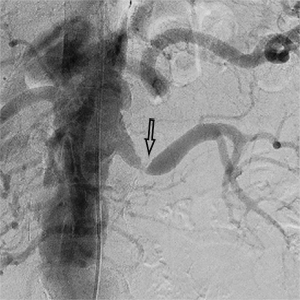

Ангіограми до та після емболізації:

міома матки до емболізації    міома матки після емболізації

Розширена звивиста ліва маткова артерія (1),

вузол лейоміоми матки (2)

Після емболізації частками: маткова артерія

збережена (1), лейоміома не контрастується (2).